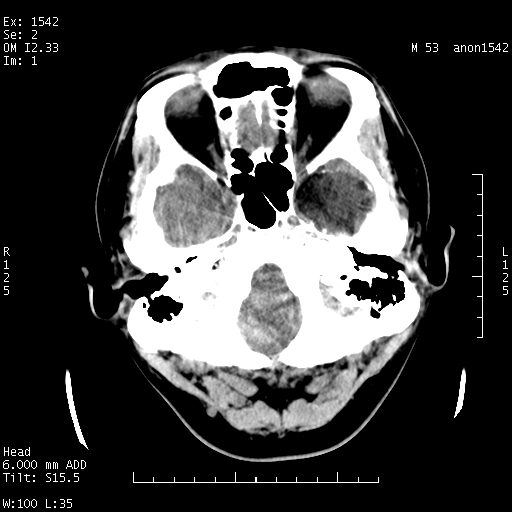

标题: CT10811:M53Y,头痛一月.其它没有什么 [打印本页]

左侧鞍旁不规则低密度,此区域和侧脑室有液平。若无外伤史。考虑左侧鞍旁表皮样囊肿自发破溃。

鞍旁颞叶低密度灶.其中散在空气影.还有侧脑室.是否考虑脑脓肿(请提供病史情况)

有肿瘤样病变破溃,沿外侧裂生长,为什么不考虑胆脂瘤?

1 囊性肿物. 2 请楼主上传介少病人资料. 3 表皮样囊肿或胆脂瘤都在考虑范围内,确切的不知ct值是多少.4了解病史后在缺定.